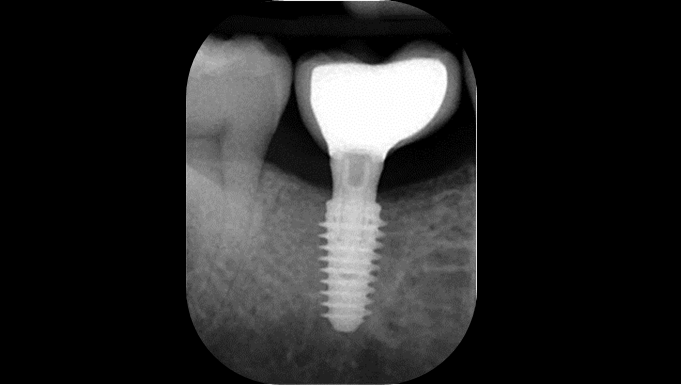

Clinical case: # 46 implant placement & GBR using i-Gen membrane for significant vertical resorption & mixed bone defect

- Courtesy of Dr. Iulian Filipov, Romania -

AnyRidge, mandibular posterior, i-Gen, resorption, bone defect, bone regeneration, space management, #46, GBR, Dr. Iulian Filipov

AnyRidge implant system, i-Gen